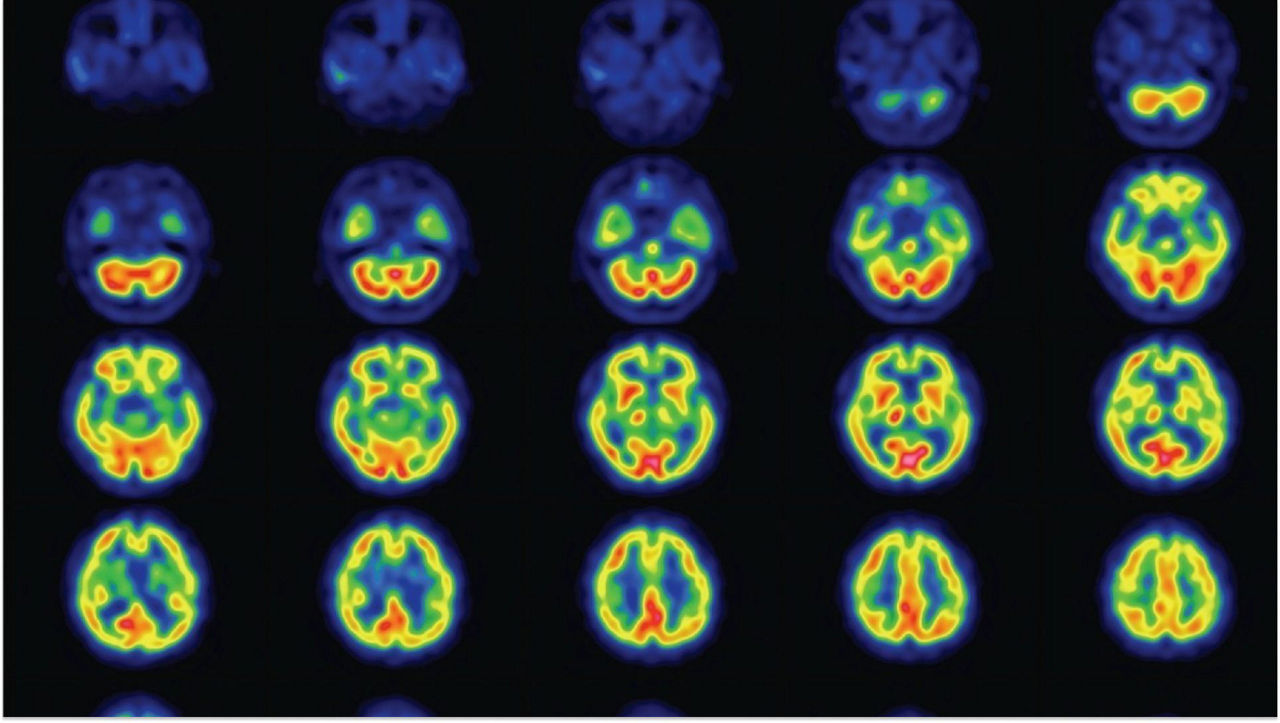

conventional-vs-myospect